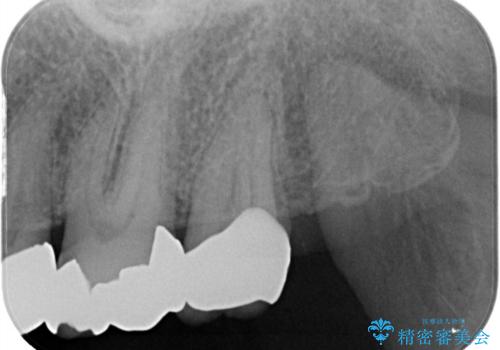

- 歯のかぶせ物が外れてしまったとのことでご来院された患者様です。左上の奥歯のかぶせ物が外れてしまった後、長期間経過したために、歯が動いて下の歯と手前の歯にぶつかってしまっていました。そのため、まずはレントゲンで内部の神経の位置を慎重に把握しながら、仮歯で歯の位置を調整させていただきました。その後、型どりを行い精密なセラミッククラウンにて治療いたしました。術後の経過は良好です。

今回、歯の位置を調整するのに、矯正治療で利用されるセパレーションゴムにて手前の歯との間を離開しています。これを行わないと、内部の神経が露出するリスクがあります。